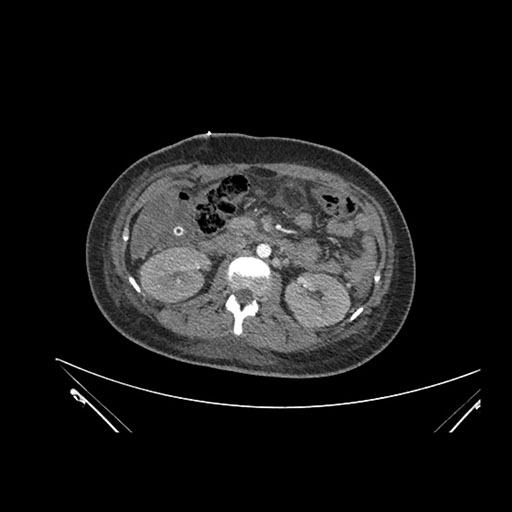

Axial Arterial

Axial Venous